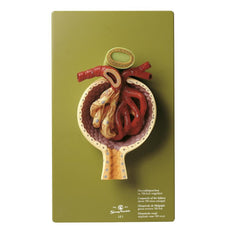

One front half of a kidney is removable from the anatomical model of the urinary system. With easy to change male insert (bladder and prostate, front and rear half) and female insert (bladder, womb and ovaries, 2 lateral halves) the Urinary System model is a great teaching tool.